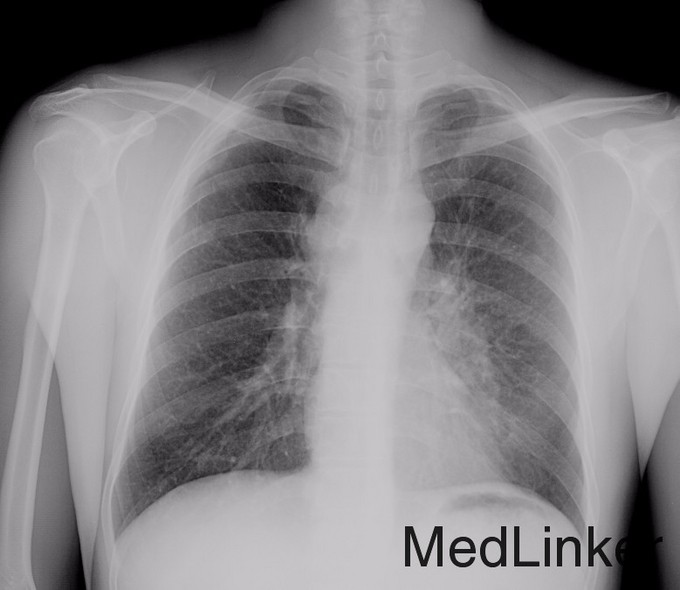

患者男,50岁,主因“咳嗽10月余,痰中带血2月。”以“左肺上叶恶性肿瘤 ”收入院。 于10月余前无明显诱因出现咳嗽,痰液为白色泡沫状,未重视,未治疗。2月余前出现痰中带少量鲜红色血,就诊于当地县医院,行胸部CT检查示“两肺结核”,予异烟肼、利福平抗结核治疗,咳嗽、痰中带血未见明显好转。为行进一步治疗转诊于承德医学院附属医院,查胸部CT及重建示:1.考虑左侧中心型肺癌继发左肺上叶舌段不张,并癌性淋巴管炎可能性大,建议支气管镜检查,门诊拟“左肺占位性病变 肺癌?”收住入院。

左肺上叶支气管内距离间嵴2个软骨环可见菜花样肿物,堵塞整个上叶支气管,触之易出血,活检。妥善止血。置入超声支气管镜,探查,第7组淋巴结及第4R组淋巴结明显肿大,分别为1.8cm,2.0cm